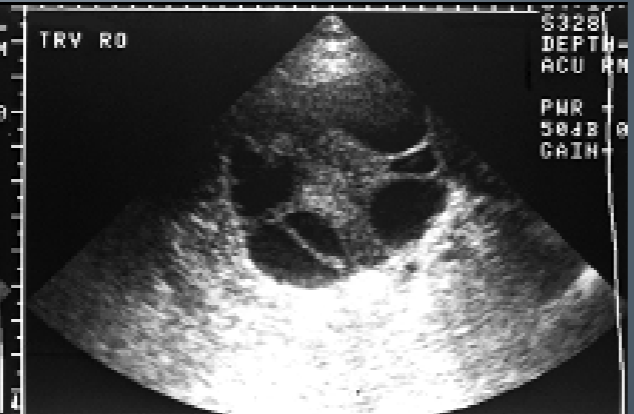

Theca Lutein Cysts tend to appear:

Multi-loculated

thin-walled

large

bilateral